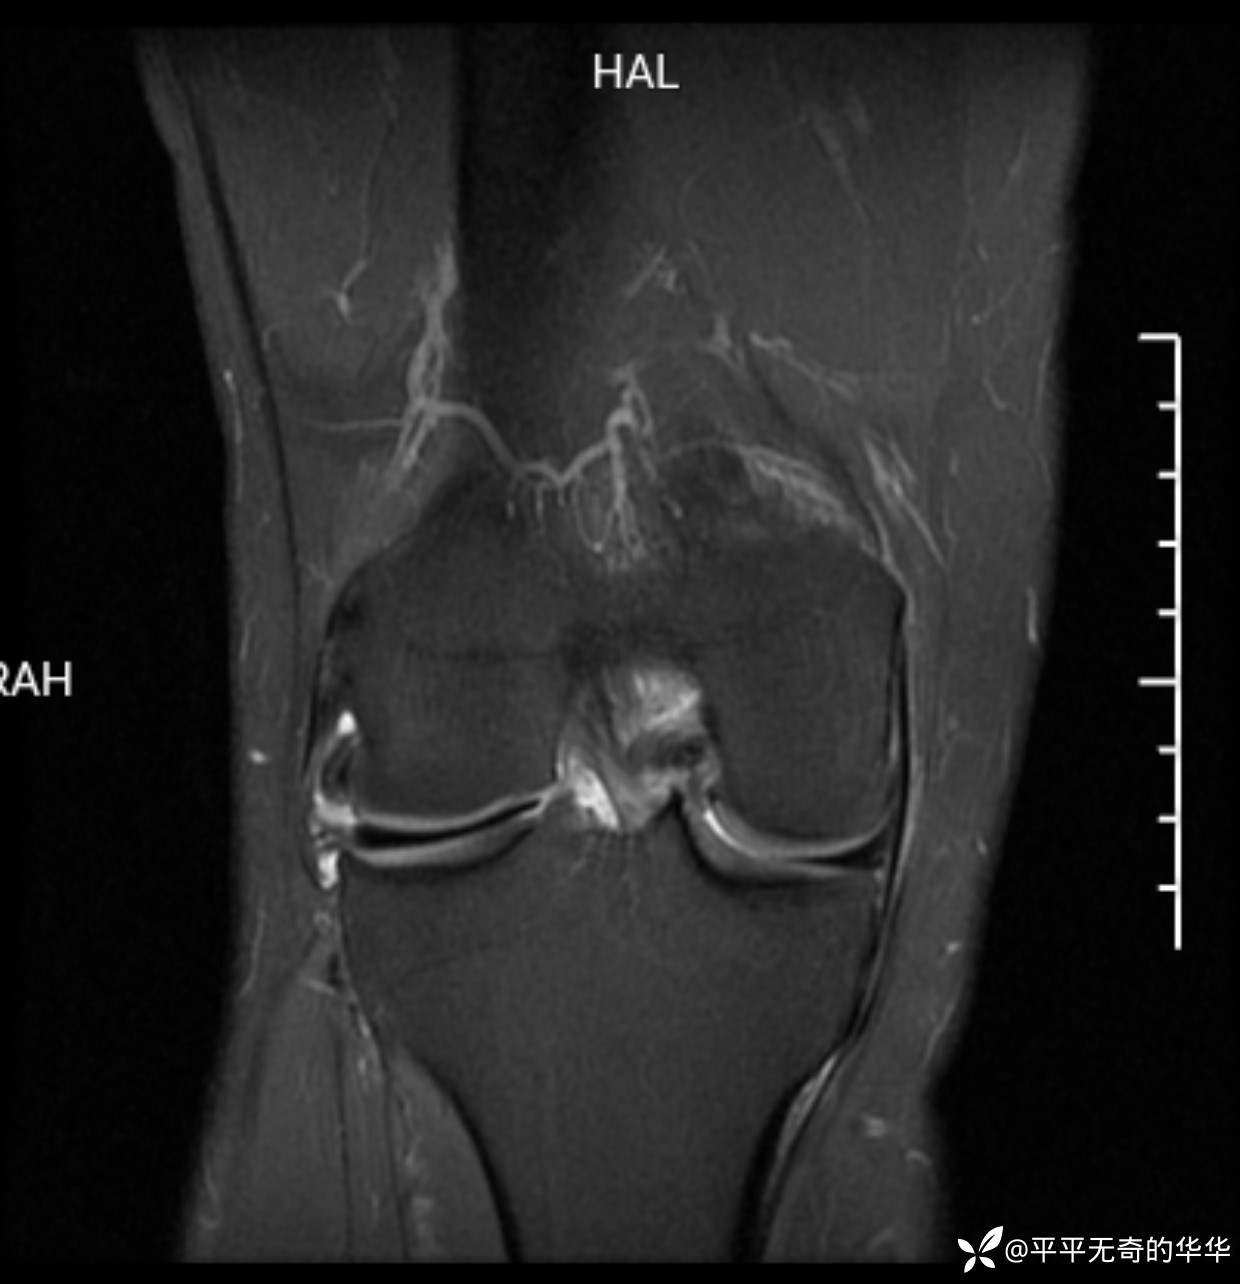

辅助检查:膝关节平片未见异常。磁共振影像如下。